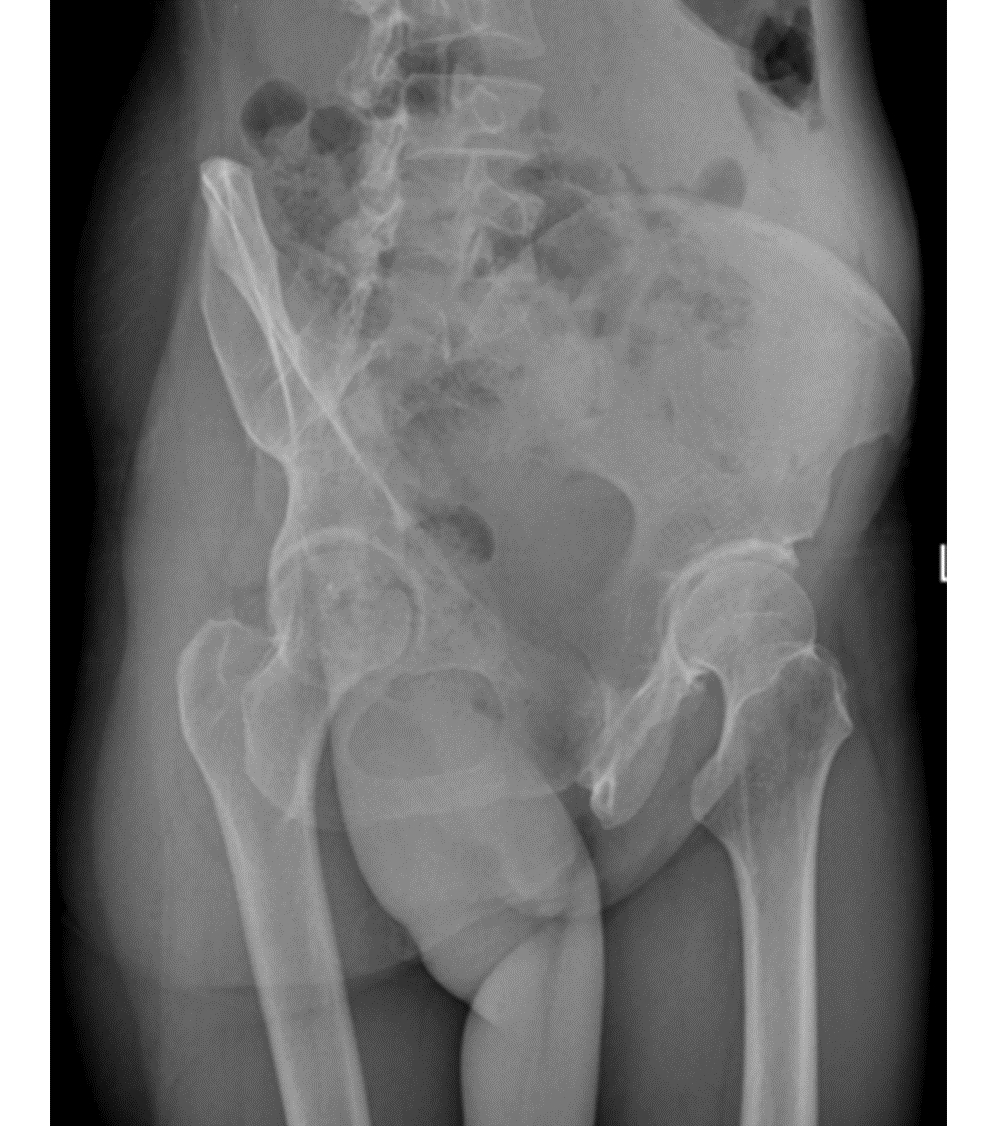

Analysis of Wilson's disease presented with osteoarticular symptoms in 14 patients

Chengwei KANG, Hongyun WO, Changchao DONG, Zhaokui YAN, Xiaobing PU

2022, 38(12): 2814-2817. DOI: 10.3969/j.issn.1001-5256.2022.12.023

Abstract(1991) HTML (1197) PDF (2195KB)(72)

Abstract: